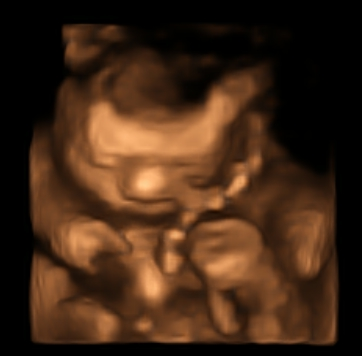

Mokkon83 Skrevet 13. januar 2011 Forfatter #788 Skrevet 13. januar 2011 (endret) Phew, for en dag!!! Først var vi hos jordmoren, hun var bare helt fantastisk koselig Mye bedre enn å gå til legen! Både Mannen og jeg felte noen tårer da vi hørte hjertelyden Fikk nytt helsekort for gravide ettersom mitt ikke ser ut til å dukke opp... Men hun har fylt på alt, så det gjør ingenting! Men denne gangen skal vi ta kopi... Hun skrev på notater: livlig barn Blodtrykket er litt lavt, men ikke unormalt.. Urinprøve var fin og vekta viste 64,0kg jeg veide 63 før jeg ble gravid, så det er jo bare fint. Hun trodde jeg kom til å legge på meg 8-10kg tilsammen. Vi kjørte rett fra jordmor til NAV, hvor vi fikk utrolig bra hjelp fra ei koselig dame Skal sende papirene våre til nav i morgen. Deilig å ha det gjort! Mellom nav og ultralyd hadde vi oss en koselig pause på kafè De hadde deilig glutenfri smørbrød, nam!! Var kjempestilig å se lille jenta vår på ultralyd (vi er nå veldig sikre på at det er ei lita tulle) hun var veldig aktiv! rene atleten, armer og bein over hodet... Ble litt uklare bilder fordi navlestrengen kastet skygge, men vi er fornøyde Vi har lyst til å komme tilbake i uke 28-29 Etter ultralyd var jeg og fikset øyebrynene endelig fresh igjen Mannen var veldig tålmodig, jeg trodde det skulle ta 15min... men det tok 45 alt i alt en kjempefin dag!!! nå gleder jeg meg enormt til ferie!! her kommer et bilde av snuppa vår Endret 13. januar 2011 av Mokkon83

Mokkon83 Skrevet 14. januar 2011 Forfatter #791 Skrevet 14. januar 2011 :rødme: Så fin hun er!! veldig rart å se henne i 3d og film..mye bevegelse og veldig atletisk..